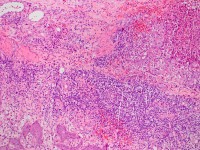

pyoderma gangrenosum. De histologie toont

supepidermale velden epitheel en oppervlakkige fistels omgeven door inflammatie.

Het ontstekingsinfiltraat vernietigt uiteindelijk de haarfollikels compleet

en ook grotendeels de epidermis en dermis tot ongeveer 3-8 mm diepte. Aan de

randen breiden deze plaques zich uit met een actieve ontstoken rand; centraal

treedt genezing op, het centrum wordt weer volledig geëpithelialiseerd maar

op een niveau onder de haarfollikels, met plaatselijk nog

cribiforme

resten van de originele epidermis. Omdat de haarfollikels volledig verwoest

worden, kan het niet nog een keer optreden in het zelfde gebied. De plaques

kunnen wel voortwoekeren over een groot oppervlak. De plaques laten littekens

achter die er uit zien alsof er een deroofing procedure heeft plaatsgevonden,

verzonken littekens bekleed met atrofische en haarloze epidermis.